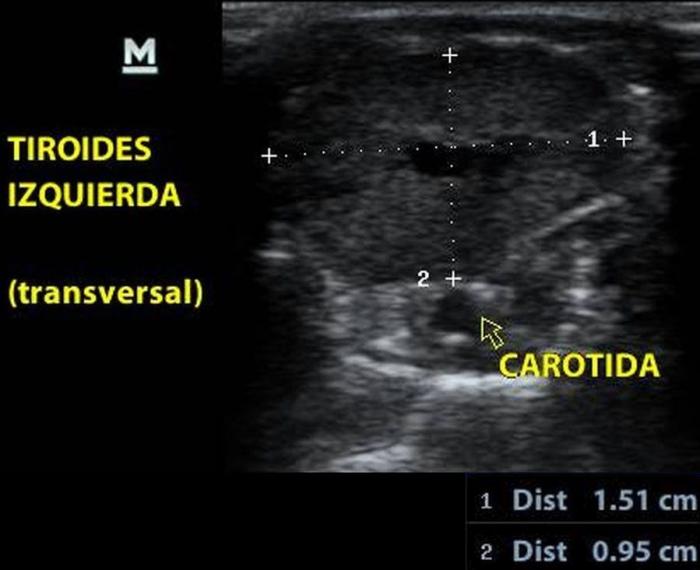

La glándula tiroides en perros y gatos está constituida por dos lóbulos situados a ambos lados de la tráquea cervical, con disposición longitudinal y una forma fusiforme o alargada que se extiende desde el cartílago cricoides hasta la entrada torácica superior2. En condiciones normales, cada lóbulo presenta contornos bien definidos, cápsula hiperecogénica delgada y parénquima homogéneo, con una ecogenicidad generalmente igual o ligeramente superior al músculo esternohioideo adyacente3,8. En la imagen transversal, los lóbulos suelen adoptar una configuración oval o ligeramente triangular (Figura 1); en longitudinal, se observa una forma alargada con extremos redondeados y orientación paralela a los vasos carotídeos y la tráquea1 (Figura 2).

La localización anatómica superficial de la glándula, junto con su estructura relativamente uniforme, facilita su identificación mediante ultrasonografía de alta resolución. Entre los reparos anatómicos más importantes para su localización se encuentran las arterias carótidas comunes (laterales), la tráquea (medial) y los músculos esternotiroideos (ventrales), mientras que el esófago puede constituir una referencia dorsal del lóbulo izquierdo15 (Figuras 3 y 4).

El índice TG/CCA es una herramienta ecográfica cuantitativa propuesta para la evaluación del tamaño tiroideo en perros, particularmente útil cuando se sospecha de hipoplasia glandular o hipotiroidismo12. Este índice se calcula mediante la medición del área transversal del lóbulo tiroideo (TG) y la comparación con el área de la arteria carótida común (CCA) adyacente, ambas obtenidas en un corte transversal a nivel medio cervical8.

Para su obtención, el animal se posiciona en decúbito dorsal con el cuello extendido. Se utiliza un transductor lineal de alta frecuencia (mínimo 10 MHz), y se realiza una imagen transversal donde se identifican claramente el lóbulo tiroideo y la arteria carótida. Se mide el área de cada estructura mediante trazo elíptico o libre, dependiendo de la morfología. La relación se expresa como TG/CCA, un valor adimensional que permite estandarizar la evaluación tiroidea en animales de distinto tamaño corporal7.

En perros clínicamente sanos, se ha reportado un valor promedio de TG/CCA de 1.53 en promedio12. Valores consistentemente bajos pueden sugerir atrofia glandular o hipoplasia, siendo útiles para apoyar el diagnóstico de hipotiroidismo en pacientes con hallazgos clínicos y laboratoriales compatibles. Según Sasaki et al. (2020), si se utiliza el valor de corte <1.12, el índice TG/CCA indica hipotiroidismo con una sensibilidad del 100 %, una especificidad del 83 % y una precisión del 90 %.